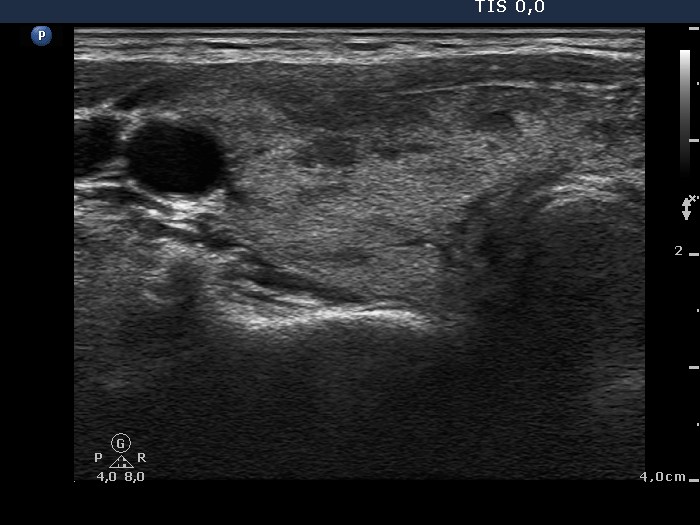

Graves' disease - Case 1049

Follow-up investigation 33 months after first visit (ultrasonographic picture 1)

Patient on daily 20 mg methimazole therapy in euthyroid state

Right lobe, transverse scan. The proportion of hypoechoic areas has significantly decreased.